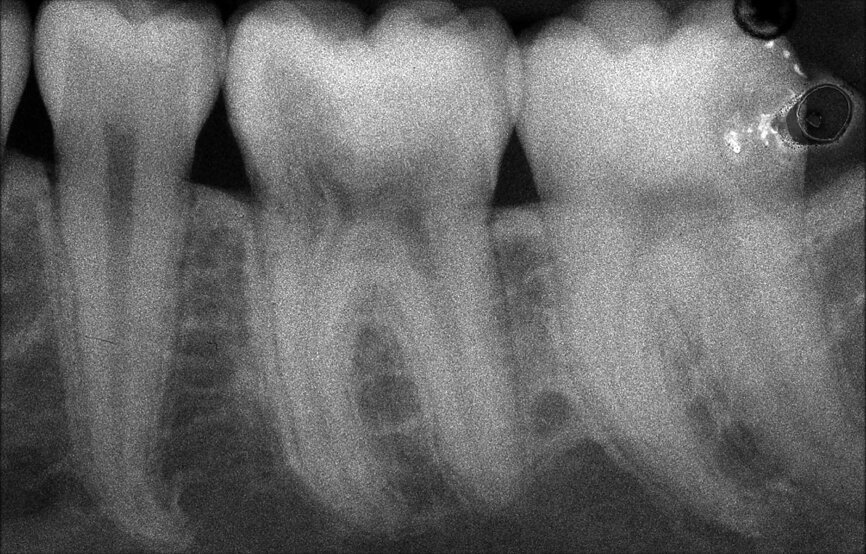

Il en va tout autrement pour la prémolaire mandibulaire présentée dans les figures 7 à 9 où, malgré l’absence de signes radiologiques de lésion et le traitement endodontique visiblement correct réalisé par un autre confrère, le patient se plaint d’une douleur persistante, qui est à la fois spontanée et déclenchée par un test de percussion de la dent. Dans ce cas, l’excellent traitement endocanalaire réalisé précédemment semble indiquer le besoin de recourir à une approche endodontique chirurgicale, susceptible de garantir un taux de réussite plus élevé que celui d’un simple retraitement. Étant donné le doute sur le diagnostic, nous avons décidé de réaliser un examen 3D et celui-ci révèle une lésion endodontique causée par un canal lingual resté sans traitement. Grâce à ce diagnostic exact, il devient possible d’envisager une intervention ciblée sur la pulpe restante, et de réaliser un traitement efficace du canal non traité.